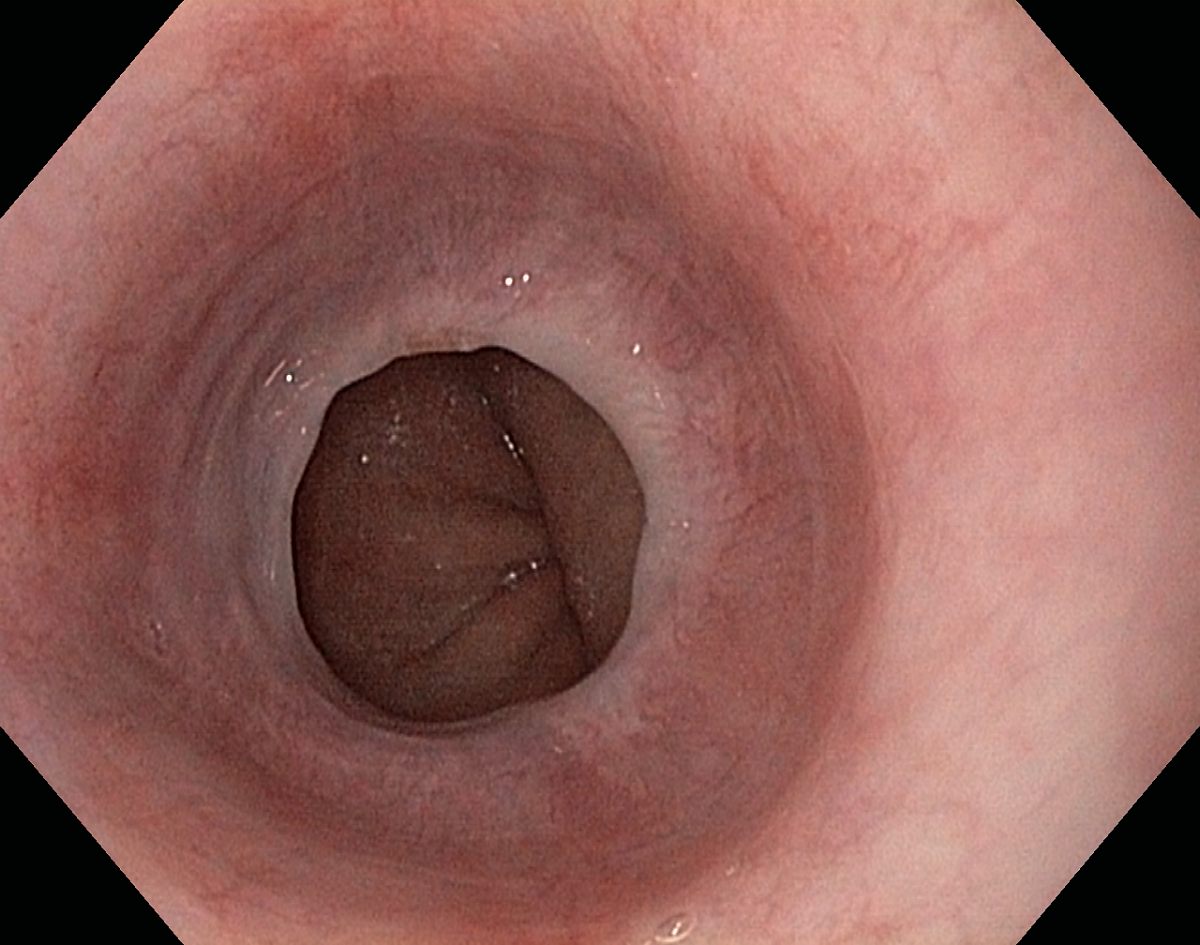

Reflux oesophagitis grade C-D according to the Los Angeles classification